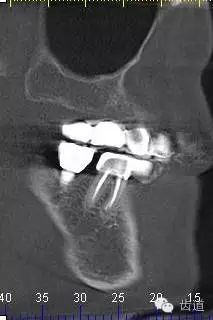

8、 左側(cè) 側(cè)面觀

9、34CBCT

10、 26,27CBCT